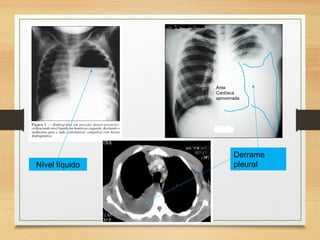

DERRAME PLEURAL

Sinais e sintomas:

Nível líquido

Derrame

pleural

Área

Cardíaca

aproximada